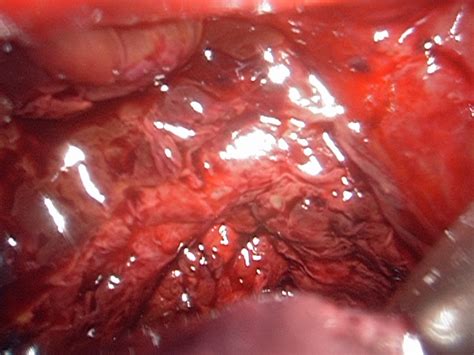

Endometriosis ovulation pain can spread to the leg or thigh and may be more severe than ordinary pain. Currently it is not known what causes endometriosis. Endometriosis happens when the endometrium, tissue that usually lines the inside of your uterus, grows outside it. Endometriosis excision surgery by an expert doctor is considered the gold standard of treatment for patients suffering from the disease. Some women only have pain around the time of their period, while others experience nearly constant pain all month long. Leg pain related to endometriosis may be more common than previously thought, affecting around 50 percent of people with endometriosis. Learn how our comprehensive approach does both. Today, we'll be talking about endometriosis ovulation pain in depth, including